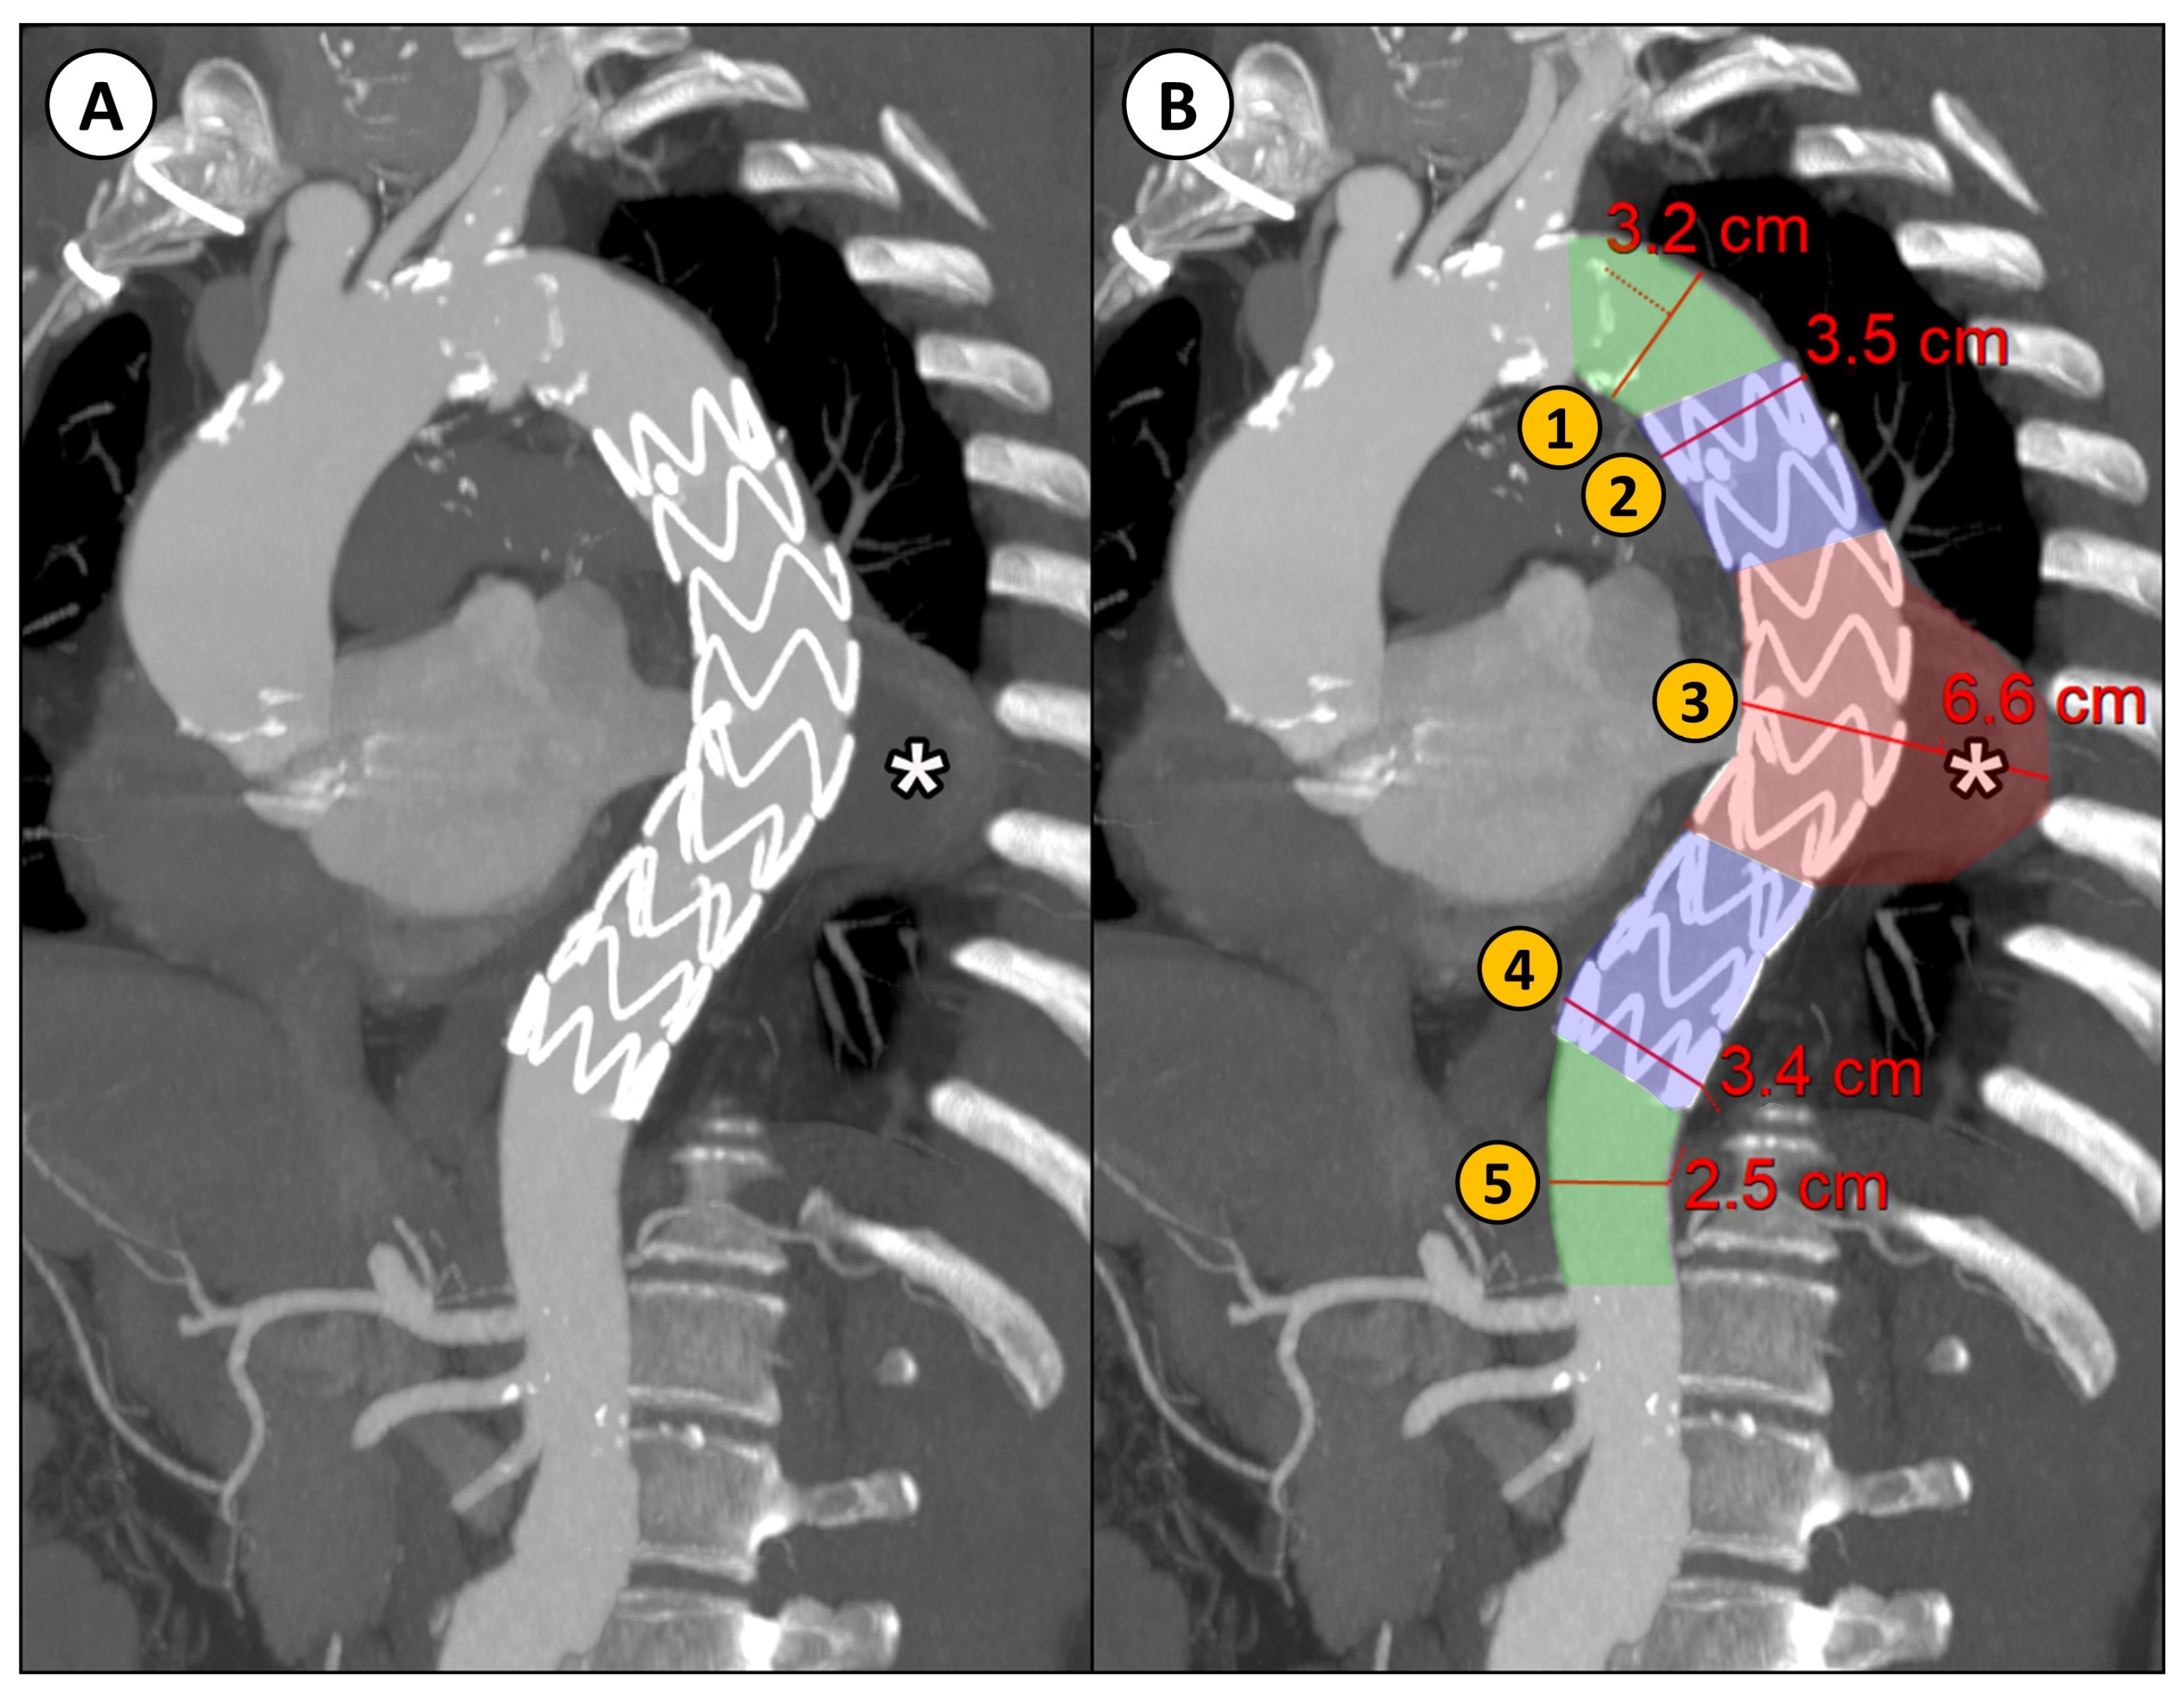

2.2. Diameter Measurement from 2D CTA Imaging

- Proximal neck (native aorta between the origin of the left subclavian artery and the proximal landing zone of the stent graft);

- Proximal landing zone of the stent graft;

- Aneurysm;

- Distal landing zone of the stent graft;

- Distal neck (native aorta between the distal landing zone of the stent graft and the origin of the celiac trunk).